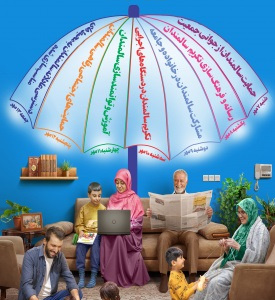

روزشمار هفته گرامیداشت سالمندان با شعار"سالمندی فعال، فردایی برای همه" (کلیک نمایید)

۰۷ مهر ۱۴۰۳شعار ملی روز جهانی سالمندان سال ۱۴۰۳: " سالمندی فعال، فردایی برای همه" عناوین روزشمار هفته گرامیداشت سالمندان (13-7 مهرماه سال1403) ردیف تاریخ ...